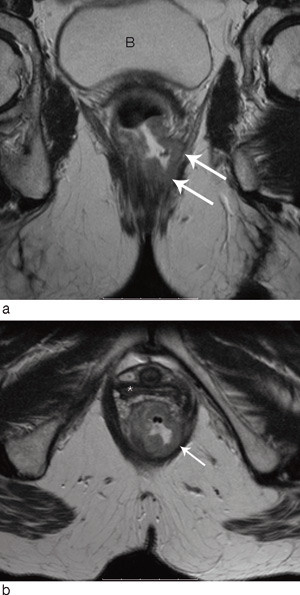

MR

MR-undersøkelse med overflatespole er i dag standard ved rectumcancer i Norge. Metoden gir en god anatomisk oversikt over hele bekkenregionen og innebærer høy grad av nøyaktighet i kartleggingen av lokal tumorutbredelse. Evalueringen av T-stadium med MR har vist svært varierende resultater, fra 65 % til 86 % (19) – (23). Overestimering av T2-tumorer og underestimering av T3-tumorer er de vanligste feilene. I likhet med endorektal ultralyd kan heller ikke MR skille en desmoplastisk reaksjon rundt tarmen fra lettgradig malign innvekst. Den mesorektale fascie, som i de aller fleste tilfeller representerer den kirurgiske reseksjonsrand, identifiseres imidlertid lett, og avstanden mellom tumor og fascie kan måles med høy grad av nøyaktighet (fig 4). Det er vist at denne avstanden er en viktigere prognostisk faktor enn T-stadium i seg selv.

Evalueringen av status for kirurgisk reseksjonsrand blir svært nøyaktig med MR (4, 19, 21, 24 – 27). Reproduserbarheten ble nylig også evaluert i en stor multisenterstudie. 679 pasienter ved 11 europeiske sentre ble undersøkt, og 311 av disse ble primæroperert. Resultatene viste 92 % nøyaktighet i evalueringen av om kirurgisk reseksjonsrand var involvert eller truet (tumor innen 1 mm fra fascien) (28) (fig 5). Man undersøkte i denne studien også hvor nøyaktig MR kunne fastslå tumors dybdeinfiltrasjon i mesorectum utenfor muscularis propria (29). Den gjennomsnittlige forskjellen mellom infiltrasjonsdybden målt med MR og dybden målt ved histopatologisk analyse var – 0,05 mm.